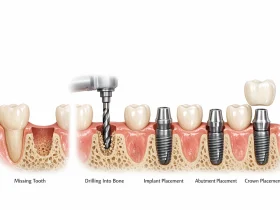

چگونه ایمپلنت فوری انجام میشود؟

فرآیند ایمپلنت یکروزه معمولاً به این ترتیب است:

- ارزیابی قبل از عمل

بررسی وضعیت استخوان فک، سلامت لثه و موقعیت دندان با تصویربرداری سهبعدی انجام میشود تا مشخص شود آیا فرد کاندید مناسبی برای ایمپلنت فوری هست یا خیر. - کشیدن دندان

دندان آسیبدیده ابتدا کشیده میشود؛ اگر پوسیدگی یا عفونتی وجود داشته باشد، این ناحیه پاکسازی میشود. - قرار دادن ایمپلنت

پایه ایمپلنت (فیکسچر) در همان روز در استخوان فک قرار میگیرد. سپس تاج موقت روی آن نصب میشود. - ادغام با استخوان (Osseointegration)

در ماههای بعدی، ایمپلنت با بافت استخوان جوش میخورد. در این دوره مراقبتهای ویژه و پیگیری دندانپزشکی اهمیت زیادی دارد.